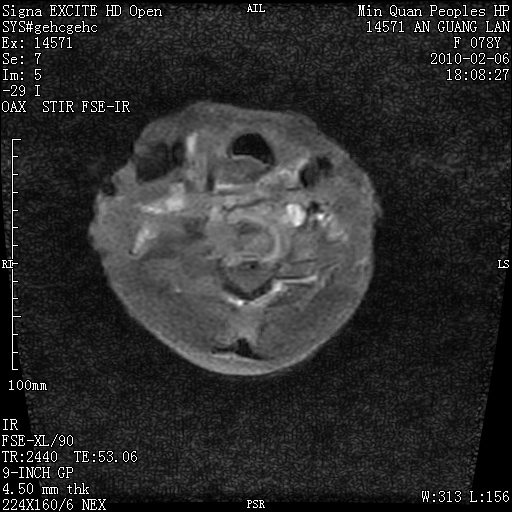

标题: MRI2763:C6、C7椎体病变性质?

f,78y,颈部与双上肢阵发性剧痛40余天。ct可见c6、c7椎体虫蚀样破坏,其间椎间隙变窄(没有图片资料可供上传)。

考虑椎体结核并椎旁脓肿。

支持 c6、7椎体结核并椎旁冷脓肿形成。

考虑:c6/7椎体结核并椎旁脓肿形成,建议增强扫描。